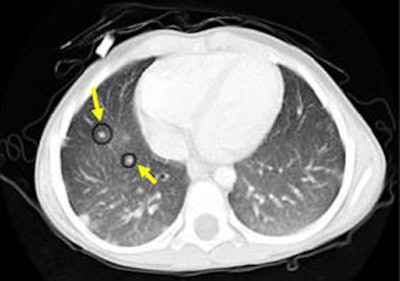

| Nodules detected by ROI detection system. Top, small nodule with inconspicuous intensity difference with surrounding lung context. Below, small well-formed nodule. Third from top, small nodule hardly distinguishable from the background and nearby thin vessels. Bottom, small irregularly shaped nodule. All images courtesy of Javad Alirezaie, Ph.D. |

![]() |

| An example of successful nodule classification. The circle encloses a true wall nodule. The rectangle surrounds a very similar wall object that is in fact a false positive erroneously detected by the group's previous CAD system. The current hybrid FP reduction approach recognizes and removes this false-positive finding. |